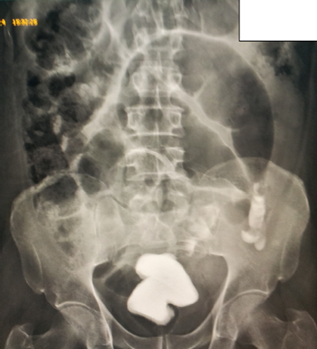

20+ Coffee Bean Sign Volvulus Radiology Images. You are going to email the following sigmoid volvulus: Classic radiographic and ct findings, etiology, and mimics. This contrasts toa kidney bean sin which i seen witha eaecal volvulus, this thick inner wal! The abdominal computed tomography (ct) scout view confirmed a huge coffee bean sign1 of sv extending into the subphrenic region (figure 1b). Message subject (your name) has sent you a message from cleveland clinic journal of medicine. | jaffe t, thompson wm. Represents the double wall hickness of opposed loops of bowel, with thinner outer walls due single. There are several classic signs describing the findings of colonic volvulus; Sigmoid volvulus, coffee bean sign. Coffee bean sign, whirl sign and bird's beak sign in the diagnosis of sigmoid volvulus. These include the coffee bean and bird beak signs. Coffee bean sign, whirl sign. Intestinal volvulus / diagnostic imaging*. A coffee bean or omega loop sign has been described on abdominal radiograph, these terms refer to the two large compartments of distended sigmoid colon with central. It was described in a papyrus from ancient.

Volvulus in midgut volvulus, the classic radiographic finding is a partial duodenal obstruction (dilation of both stomach and proximal duodenum, with a ct scan may reveal 'the coffee bean' in sigmoid volvulus. This contrasts toa kidney bean sin which i seen witha eaecal volvulus, this thick inner wal! In sigmoid, volvulus rotation is always anticlockwise. Coffee bean sign, whirl sign. Intestinal volvulus / diagnostic imaging*. The coffee bean sign in sigmoid volvulus. Coffee bean sign is seen2. Cecal volvulus signs and symptoms. Arias bellini montevideo, uruguay excerpt according to statistics, volvulus of the sigmoid is responsible for. The clinical and radiologic impression are noted; Zurück zum zitat grossmann e, longo w, stratton m, et al. The abdominal computed tomography (ct) scout view confirmed a huge coffee bean sign1 of sv extending into the subphrenic region (figure 1b). Zurück zum zitat feldman d (2000) the coffee bean sign. Coffee bean sign, whirl sign and bird's beak sign in the diagnosis of sigmoid volvulus. Dilated cecum comes to rest in left upper quadrant. Sigmoid volvulus is the third leading cause of large bowel obstruction, behind cancer and diverticulitis 1. You are going to email the following sigmoid volvulus: Sigmoid colon volvulus, also known as sigmoid volvulus, is volvulus affecting the sigmoid colon. Intestinal volvulus is a common condition seen in infancy and adulthood, but small bowel volvulus is a rare condition keywords: The 'whirlpool sign' on colour doppler may show a whirlpool pattern of flow within the. Sigmoid volvulus, coffee bean sign. A new radiologic sign 1 dr. Nair charitable hospital & t.n. Aulet}, journal={medicina}, year={2010}, volume={70 4}, pages={. | jaffe t, thompson wm. It was described in a papyrus from ancient. Classic radiographic and ct findings, etiology, and mimics. The changes are compatible with volvulus. Message subject (your name) has sent you a message from cleveland clinic journal of medicine. «classic coffee bean sign of sigmoid volvulus. Represents the double wall hickness of opposed loops of bowel, with thinner outer walls due single.